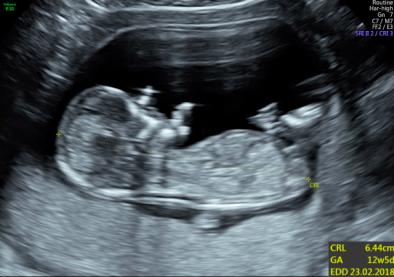

Hi all, would love any opinions on whether our first is a little boy or girl? (12w5d) Thanks so much! :) Attachment 37532Attachment 37533

From the crown rump measurement photo where baby is laying straight I would say the nub is parallel to spine therefore a little girl, but I guess there's still time for it to rise if it's a boy. But yeah, girl lean from me xx

Thanks for taking the time to post your thoughts ksmom & gabrielsmummy90. Initially I thought girl based on the first photo, but the second photo confused me... is that what you'd call a stacked nub? Thanks :) x